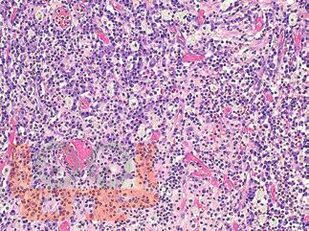

В атласе подробно изложено цитологическое и гистологическое описание всего спектра патологических изменений ткани молочной железы: неопухолевые, пролиферативные процессы, предраковые поражения, доброкачественные и злокачественные опухоли. Кратко представлены данные об этиологии, о патогенезе, молекулярной генетике, клинической картине и лучевых методах исследования различных поражений молочной железы. Подробно описаны дифференциальная диагностика и возможные ошибки морфологической диагностики. Атлас иллюстрирован большим количеством микрофотографий.